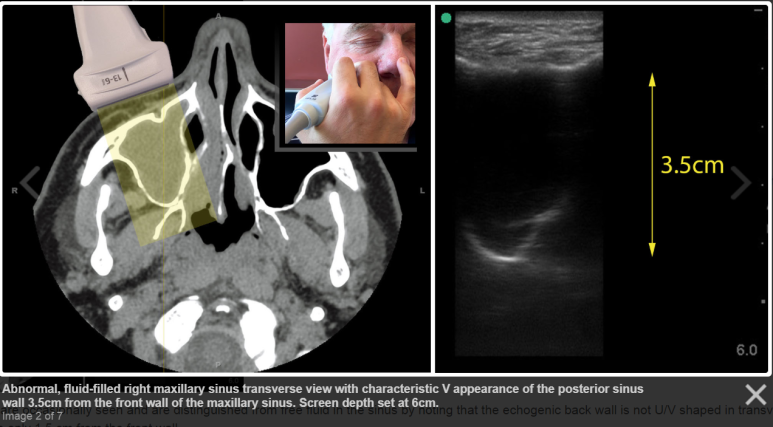

물이 찬 부비동의 CT / US image